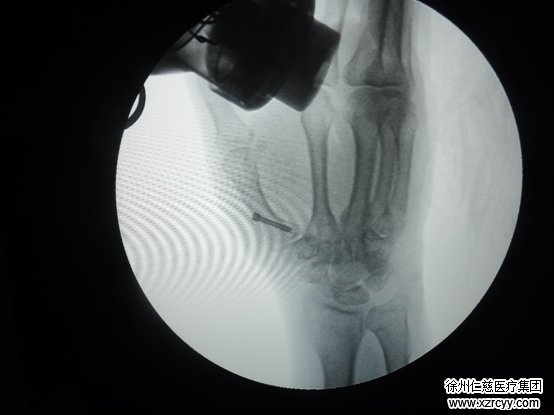

术中

一颗螺丝钉解决问题

齐伟亚主任介绍,“Herbert螺丝钉内固定是一种松质骨加压固定的新型螺丝订,由Herbert设计,于1977年开始应用在临床上。该螺丝钉的特点为两端有螺纹,中间无螺纹,头部无螺帽、直径为4mm,可以埋入软骨下,起到加压作用。”

与克氏针内固定、钢丝内固定、微型钢板内固定相比,Herbert螺丝钉稳定性较好,并允许早期活动关节,外固定平均使用4周,有的甚至可不用外因定,亦不必做二次手术取出螺丝钉。是关节内骨折较理想的内固定材料。

4月11日,收治入院第二天,李女士被推入手术室。术中,通过2毫米的切口,置入Herbert螺钉内固定。术后第二天,李女士指间关节便可进行活动。